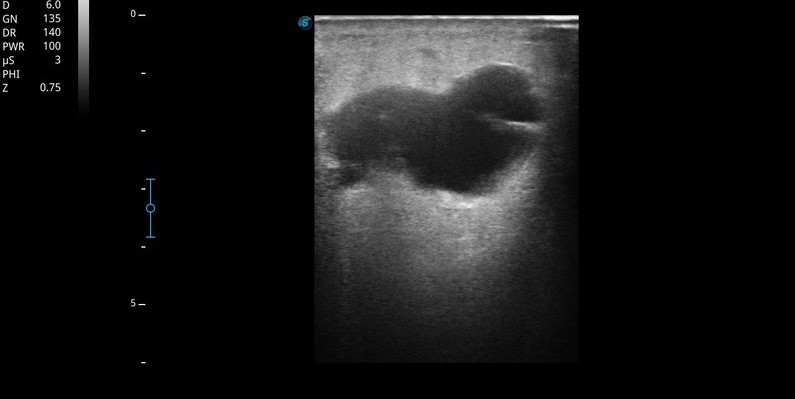

Ecografía MII: Sistema venoso profundo permeable, compresible en todo su recorrido, sin contenido hiperecogénico en su interior. Sistema venoso superficial permeable. Se objetiva a nivel de tejido celular subcutáneo de región interna de tercio superior de muslo izquierdo, colección anecoica, tabicada, no vascularizada, con algunos ecos en su interior, de unos 3-4 cm, con sombra acústica posterior. Importante edema en empedrado en pierna izquierda compatible con celulitis.

• Punción de colección: Extracción de contenido seroso.